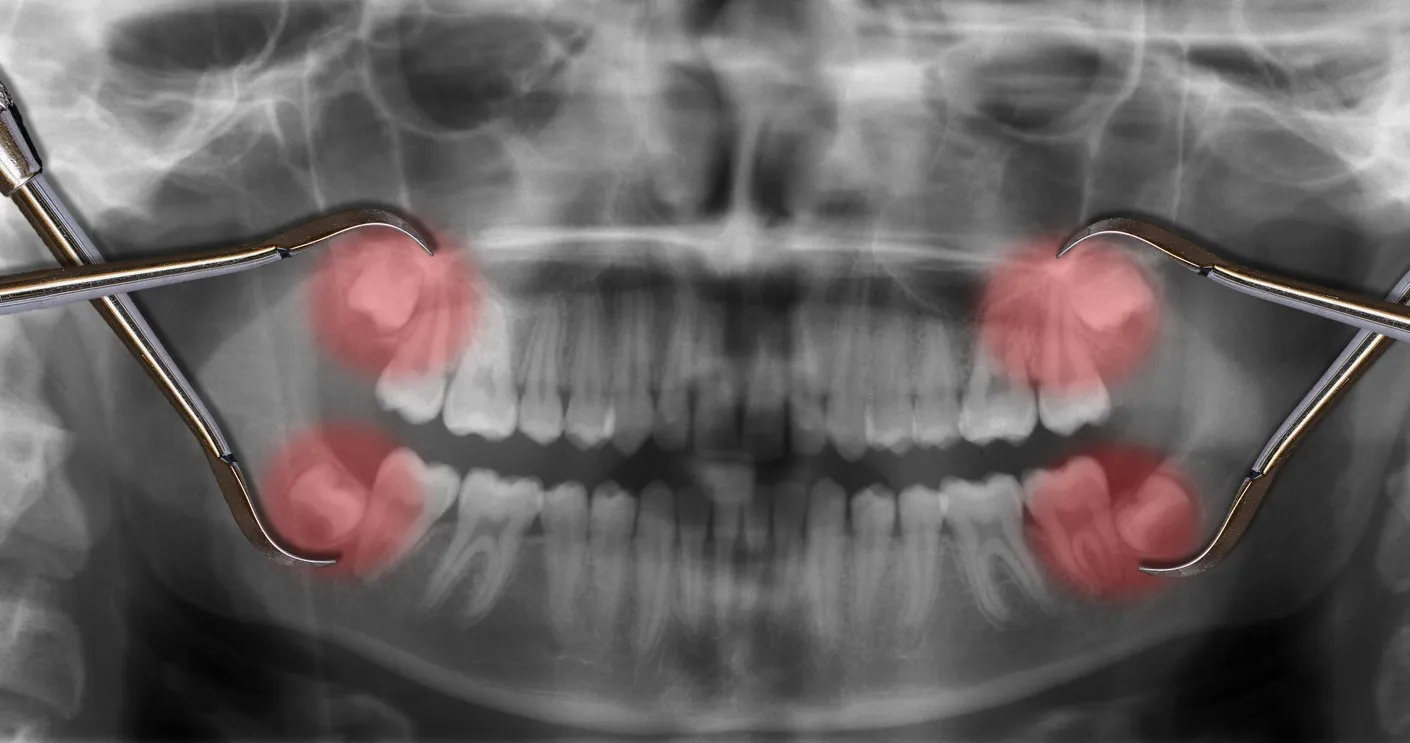

Dhëmballët janë të futura në majë dhe në fund të nofullës. Të rriturit shpesh kanë 4 dhëmballë. Mjekët këta dhëmbë i kanë shpallur të panevojshëm, andaj shpesh i nxjerrim.

Nxjerrja e tyre megjithatë mund të ketë pasoja. Për shkak të lidhshmërisë së gojës dhe pjesëve të tjera të trupit, disa njerëz ndiejnë shtangim të përhershëm pas operacionit.

Nxjerrja e paarsyeshme e tyre mund të shkaktojë infeksione, deri te lëndimi i nervave të fytyrës, dhembje, gjakrrjedhje të pakontrolluar dhe gjithsesi shërim të gjatë.

Për shkak të këtyre simptomave, nxjerrjen e dhëmballëve kur nuk është e nevojshme nuk e rekomandojnë stomatologët. Ata thonë që më së miri është të pritet që të shfaqet problemi, sepse te shumica kurrfarë problemi nuk shfaqet.

Ekspertë mjekësorë kanë konstatuar që numri i intervenimeve kirurgjikale është zvogëluar për 60%. Pra, më shumë se gjysma e operacioneve të nxjerrjes së dhëmballëve vërtet është e panevojshme!

Nxjerrja preventive e dhëmballëve ka shumë të meta. Më së miri do të ishte që më parë të konsultoheni me stomatologun dhe të mësoni sa janë shanset që të keni probleme me dhëmballët.